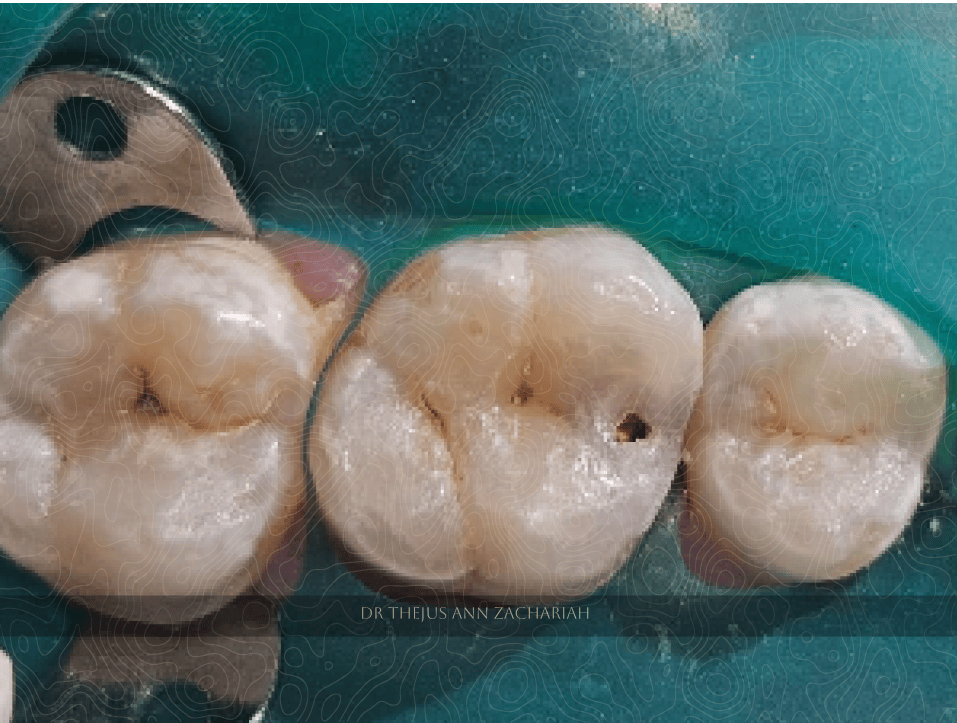

Post-Operative

alt text